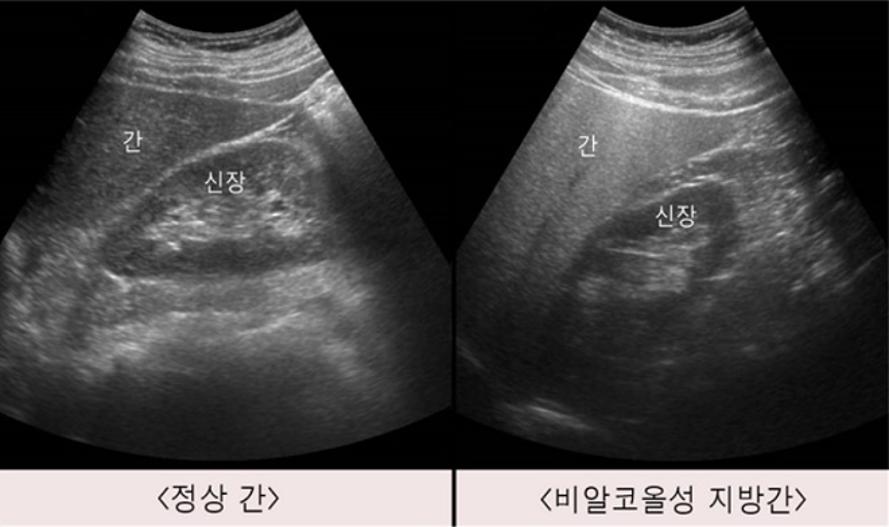

비알코올성 지방간, 대장암·유방암 위험 2배

사진 : 서울아산병원

지방간은 간에 지방이 5% 넘게 쌓인 상태를 말한다. 우리나라 성인 3명 중 1명이 가지고 있을 정도로 매우 흔한데, 그 중 대부분은 비만, 당뇨, 고지혈증 등 다른 신체 질환들과 관련된 비알코올성 지방간이다.